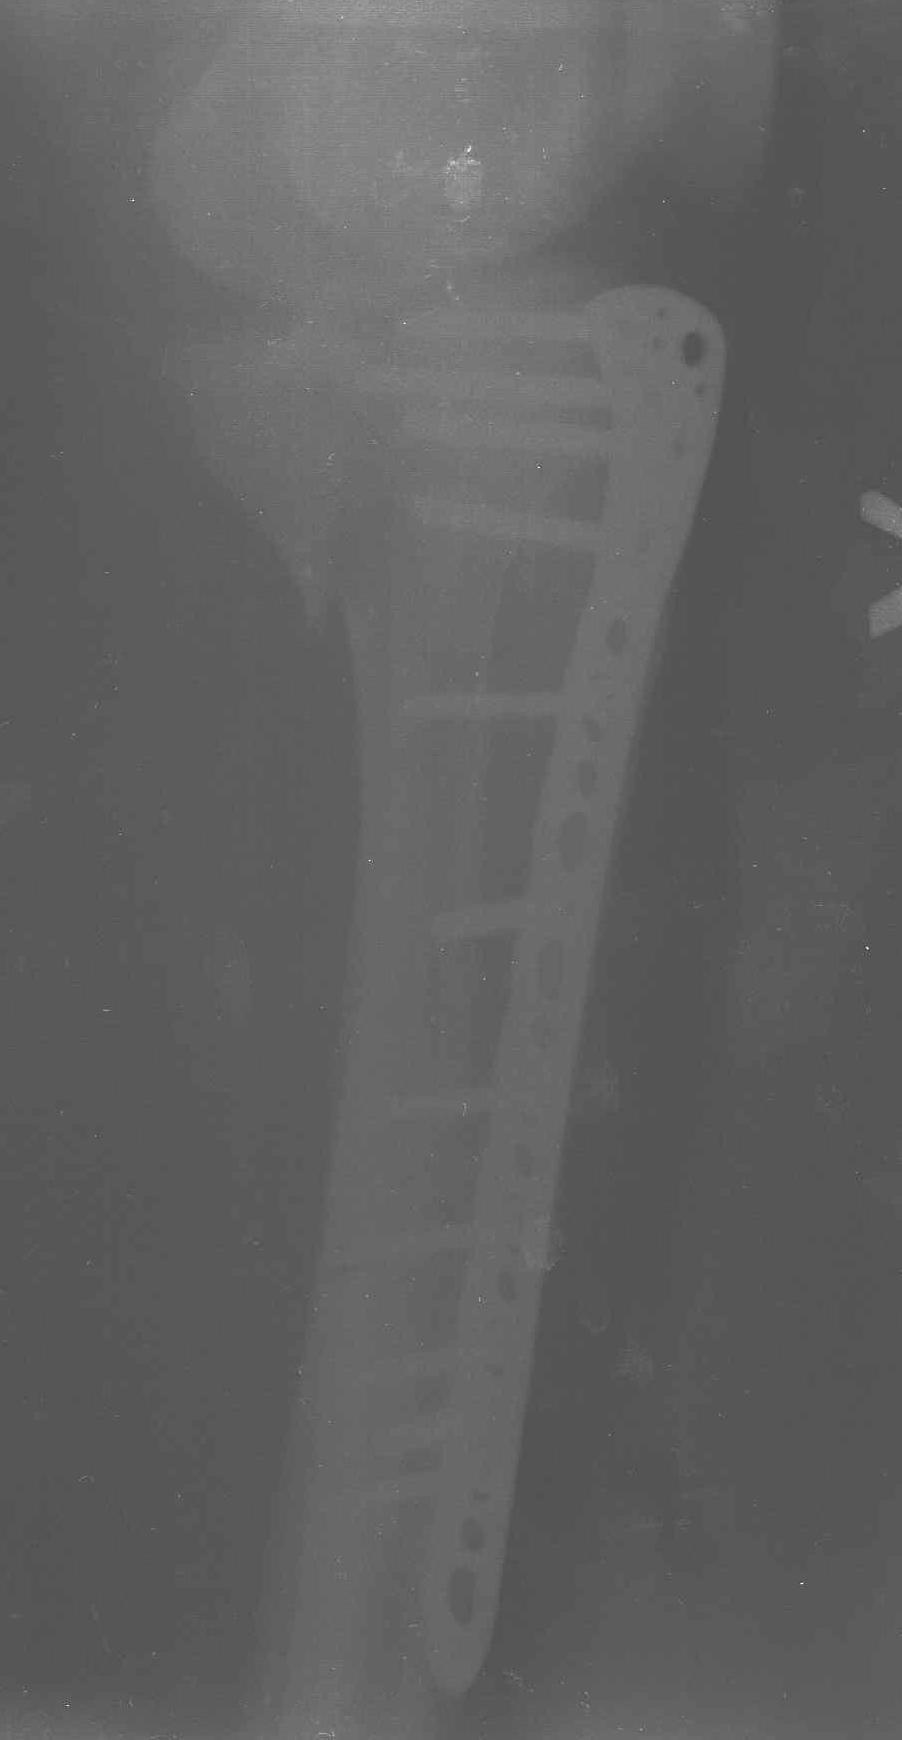

Уважаемые коллеги! В прошлую пятницу больной прооперирован - как и планировалось мыщелковая LCP от ChM. Малоинвазивно не получилось - один большой доступ :(. (но с минимальным скелетированием б/б кости). Наружный мыщелок собрали, но по контролю видно, что задне-медиальный отдел метаэпифиза смещен. Фиксировать не стали (?). 4-е сутки после операции - по м/тканям без проблем. Дополнительная иммобилизация синтетическим тутором.

P. S. перелом диафиза на контроле не совсем захвачен, но проблем там нет. Приношу извинения за низкое качество Р-грамм - выполнены на сканере (фотоаппарат не работает :)) .

Трудно поверить, что разрекламированная Ортопедическая школа Восточной Украины позволяет такие странные снимки? На прямом снимке сохранен общий контур плато, но не известна судьба импрессии суставной поверхности. На полубоковой?, оставлен без репозиции задне-медиальный отдел, и навряд ли после такой фиксации можно удовлетвориться результатом.

Такая ситуация характерна для многих, когда принимается ошибочное решение, т.е пытаются фиксировать одним имплантом переломы двух мыщелков. Латеральная пластина приемлема только для тех случаев, когда сохраняется интактным медиальный диафизарный кортекс и отсутствует фрагментация на верхушке медиального перелома.